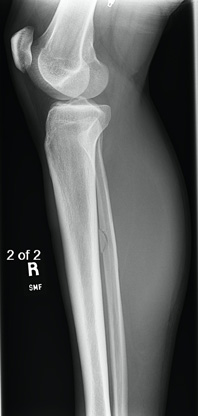

Obtaining images at the initial visit is important to rule out a Maisonneuve fracture. Plain radiographs are vital as they can identify fibular fractures, fibular shortening, and any abnormal spacing between the tibia and fibula caused by syndesmotic disruption. Traditionally, ankle radiographs are taken in anterior-posterior (AP) view, stress view (abduction and external rotation), mortise view, and lateral view (Figures 3a-d). It is necessary to acquire AP and lateral radiographs of the knee with tibial and fibular views to determine the extent of the fibular fracture (Figures 4a-b). When reviewing the radiographs, it is important to measure the tibiofibular clear space, medial clear space, and tibiofibular overlap. The tibiofibular clear space is measured at 1 cm above the talus and measures the distance between the medial border of the fibula and the lateral border of the tibia. Typically, the tibiofibular clear space is less than 5-6 mm on the AP and mortise views. Anything greater than 10 mm is diagnostic of a syndesmotic injury.

Figure 4a: AP View of the Knee with a Fibular Fracture

Figure 4b: Lateral View of the Knee with a Fibular Fracture